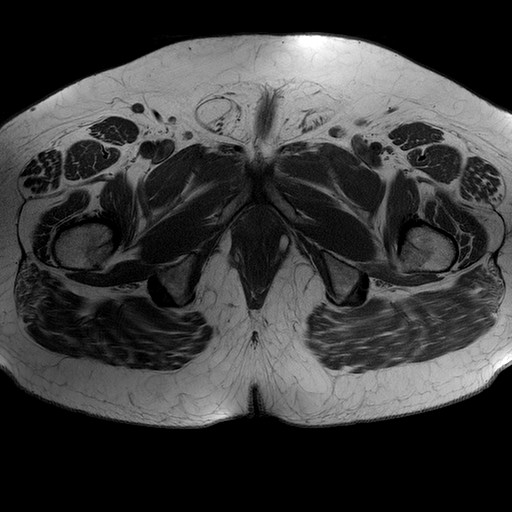

Esami: RMN BACINO

Evidenti e simmetriche alterazioni osteofitosiche in regione coxo femorale con riduzione delle rime articolari. Degenerazione completa del cercine glenoideo. Non attuali segni di versamento articolare. Non segni di edema osseo che escludono attuale algodistrofia od osteonecrosi. Lieve e simmetrica riduzione del trofismo della muscolatura glutea.